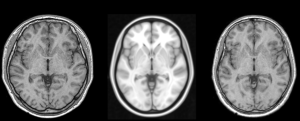

Developed SOP SOP(Standard Operating Procedure) Optical Images EM MR CT EPhys(EEG, MEG) Others Developed SOP SOP(Standard Operating Procedure) Optical Images EM MR CT EPhys(EEG, MEG) Others